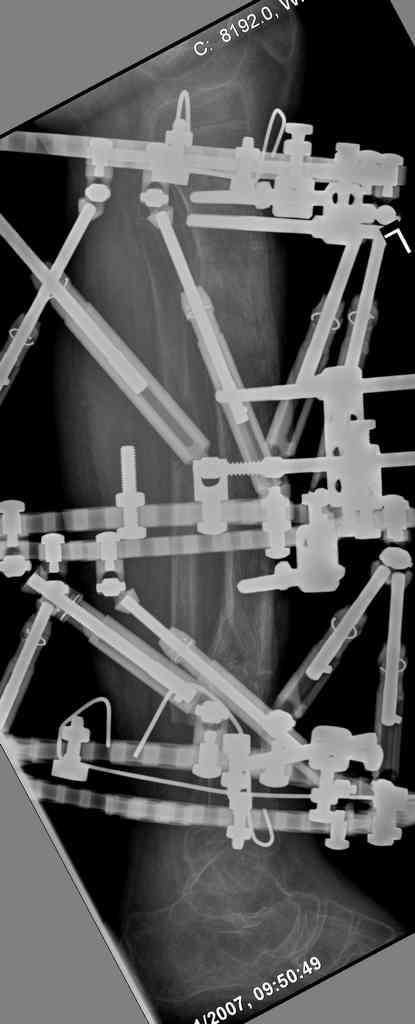

4. Никто не назвал методику, которая мне представляется наиболее удачной - тибиализация малоберцовой кости. Пластинку, конечно, придется убрать. Нужно наложить кольцевой Илизаров,

томировать малоберцовку на уровне дефекта, закрыто пересечь большеберцовую кость у основания острого края проксимального отломка - и подтянуть фрагмент малоберцовой кости в зону дефекта большеберцовой спицами с упорными площадками. Не обязательно при этом выводить строго в центр, достаточно сращения при боковом касании отломков - малоберцовая кость оттеснит как раз "сосульку" в сторону, и томированные края берцовых костей срастутся между собой. Есть еще ряд нюансов - готов расписать со схемами в случае, если будет принято решение в пользу этой методики.

Реализовал описанную выше методику, и в итоге вот что получилось. Высылаю лишь прямые проекции,

в боковых тоже всё в тему.

Очень пригодились карбоновые кольца (Джолдас -огромное спасибо, я твой должник!!!), поскольку остеопороз дистального отломка был просто невероятный. На цифровом рентгене с трудом угадывались контуры.

Рентген в процессе перемещения - внизу карбоновые кольца, тракция фрагмента спицами с упором.

внешний вид в аппарате - не завершающем этапе, сначала стопа тоже была фиксирована в аппарате.